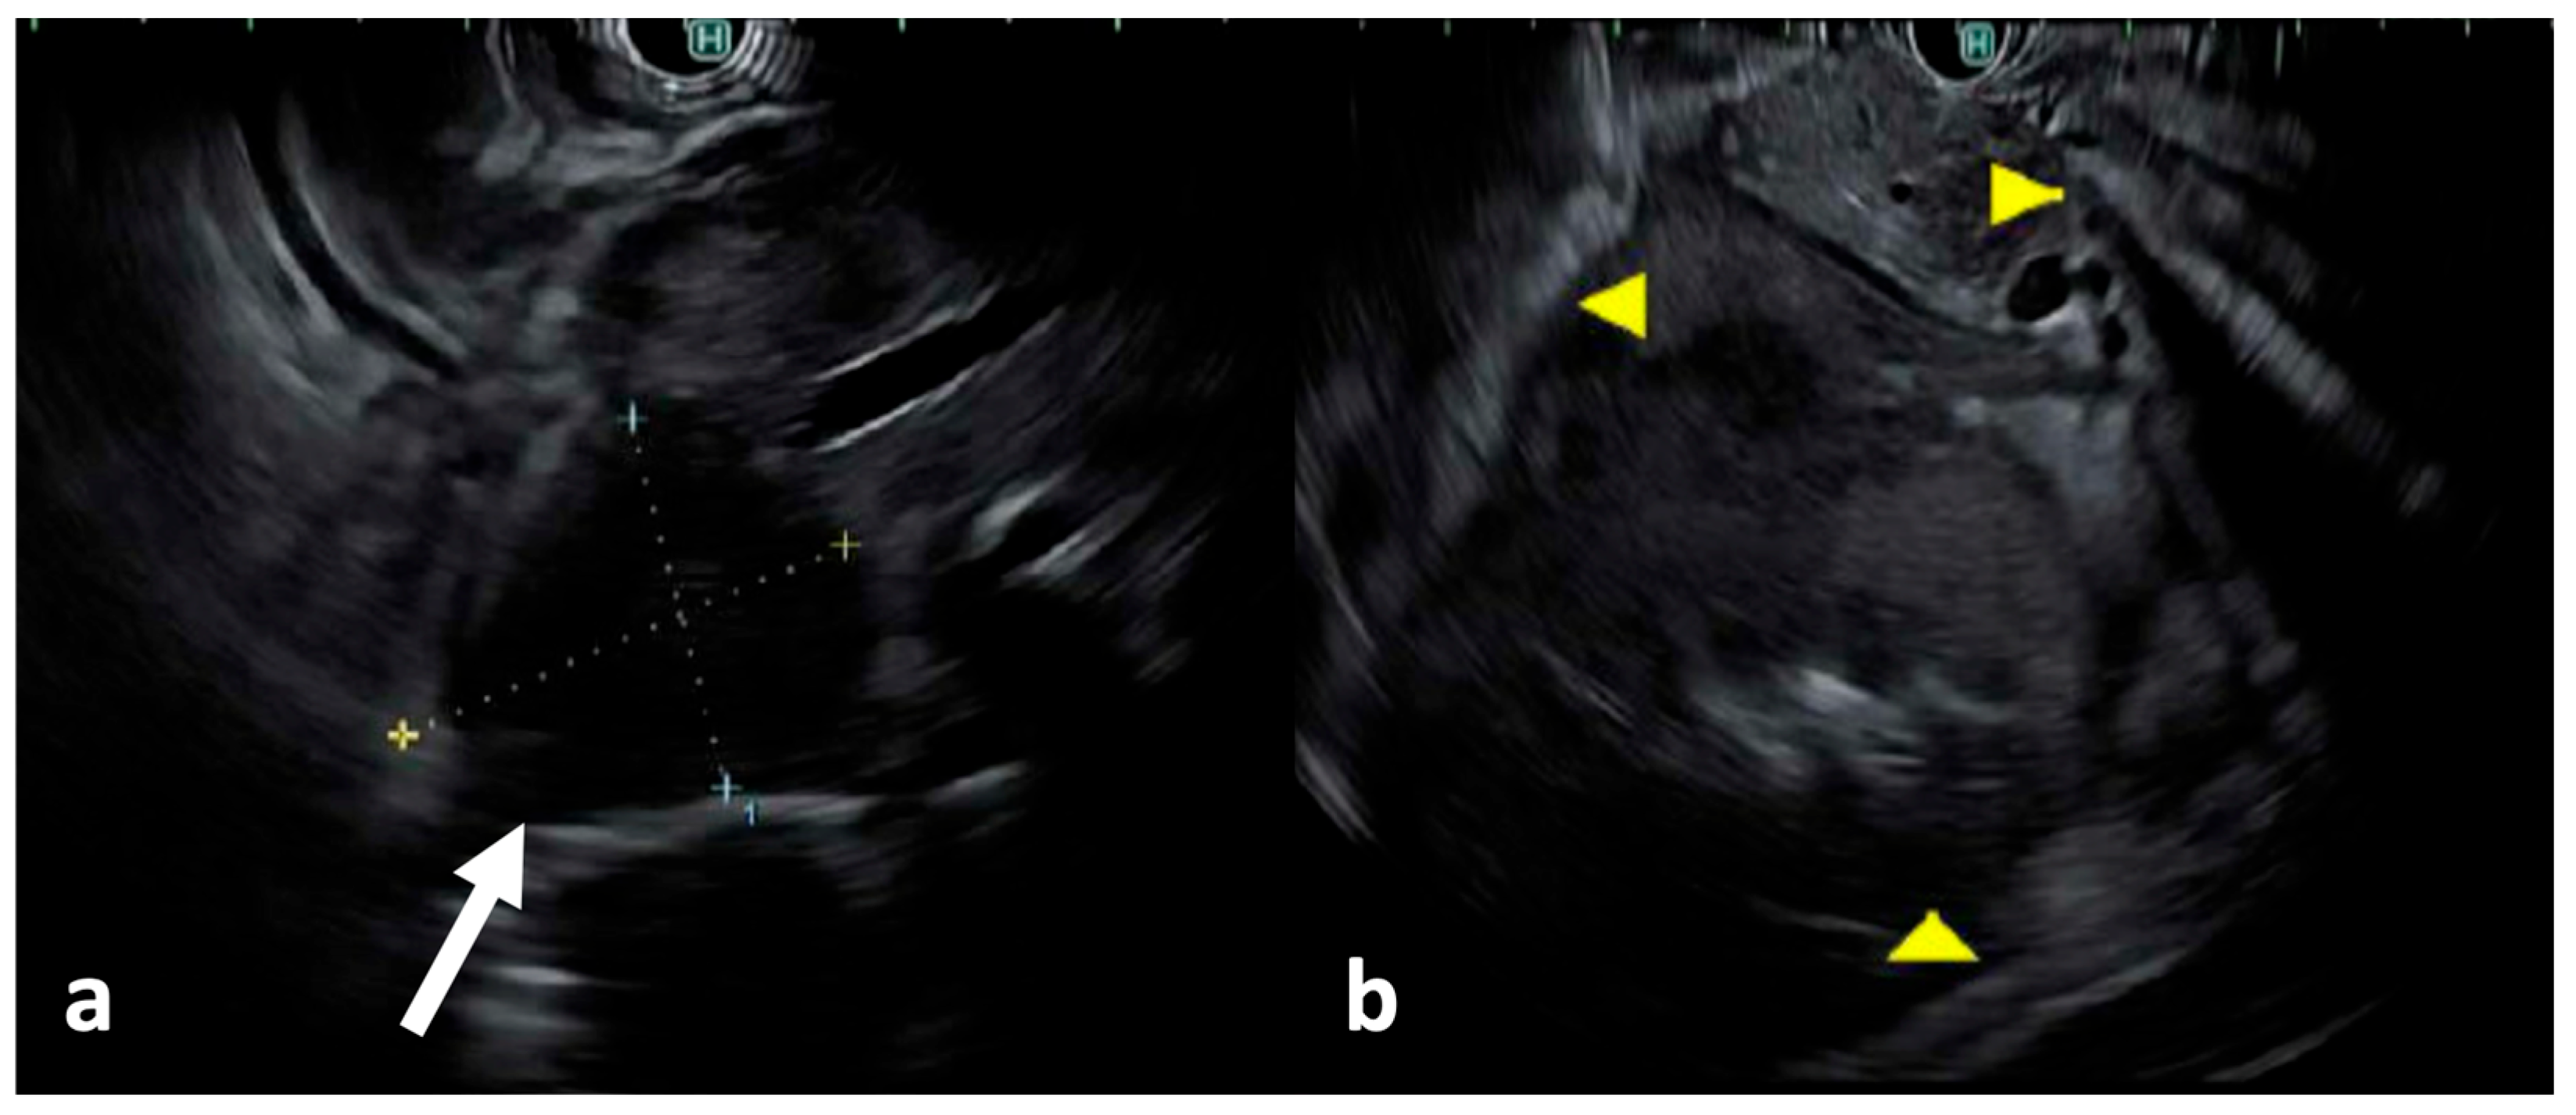

2. Case Presentation